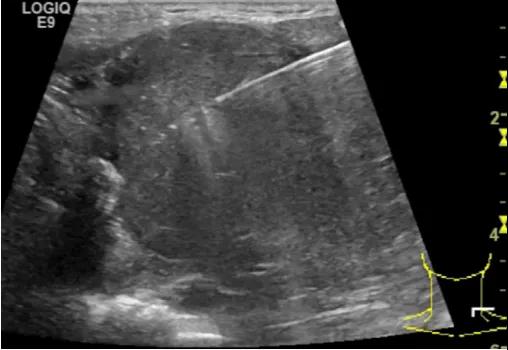

第四例是胸腺癌化妆包,术后、化疗之后淋巴结转移,肿块范围巨大,99mm*61mm,边界不清,呈浸润状,肿块包绕颈动脉,颈内静脉压闭,症状明显。由于患者放化疗也不敏感、血供非常丰富,于是采取多点姑息性消融。姑息性消融后未实现完全消融,病灶大片坏死,肿胀疼痛得到明显的缓解,后续患者未再来复查。

(病例4图例)